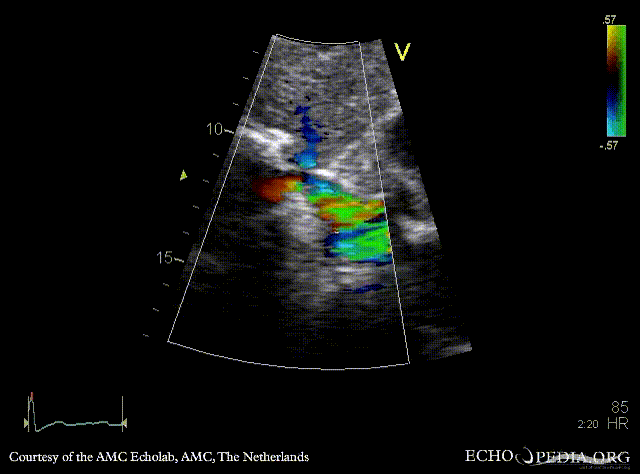

Obstruction of vena cava inferior

Subcostal view: obstruction of vena cava inferior from outside the heart Subcostal view with Color Doppler: high velocity flow in vena cava inferior